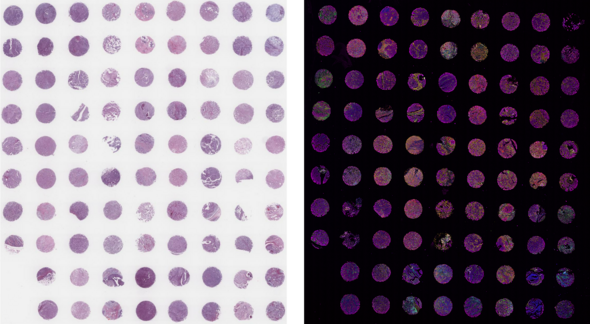

• Capable of large tissue microarrays

• Low plex, high throughput, 80 slide capacity